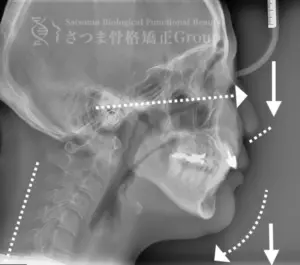

渋谷TMJ歯科クリニックでは、頭蓋および頸椎の歪みが顎位(あごの位置)と咬合(噛み合わせ)の乱れを引き起こし、その結果として顔の歪み、顎関節症、食いしばり、ストレートネックによる強い肩こり、さらには自律神経の乱れへとつながると考えています。

これらの問題を正確に評価するため、当院では セファロシステムによるレントゲン撮影(X-ray images) を行っています。

セファロ撮影によって 顎関節・頭蓋骨・頸椎の位置関係を客観的に可視化でき、施術前の状態を科学的に把握することが可能となります。

• 顎位のズレ

• 咬合の乱れ

• 頭位・頸椎姿勢のバランス

• 筋肉・関節の負担部位

施術の前後で撮影したレントゲン写真を比較することで、改善の度合いや変化を一目で確認できます。